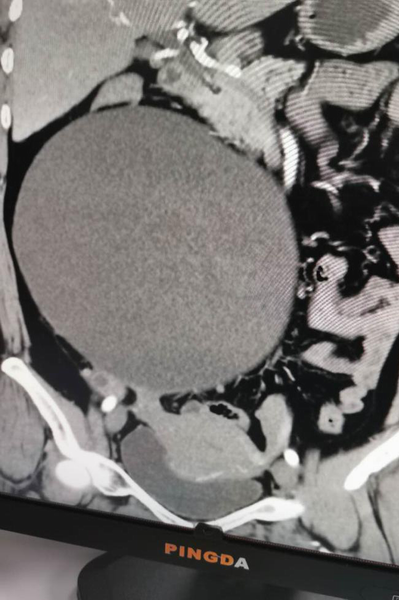

近半月腹部悶脹感加重,仰臥不能,伴頭暈、頭痛、四肢乏力,心悸胸悶、納差食少,當地縣人民醫院檢查發現盆腹腔有一巨大包塊性質不詳,進一步CT檢查示:右側腹腔巨大包塊影(20x18cm),診斷為:1、盆腹腔巨大包塊性質待查;2、高血壓3級極高危組;3、高血壓性心臟病;4、混合型高脂血癥;5、子宮肌瘤等多病。因患者盆腹腔包塊較大,合并基礎疾病較多,建議到上級醫院行手術治療、明確性質,遂于2020年10月19日就診于我院并收住婦科。

經充分術前準備后于10月23日在全麻下由婦科聯合外科團隊緊密配合下成功開展盆腔巨大包塊切除+子宮肌瘤剝除術,術中切除來源于右側附件(卵巢)巨大包塊約21x19x13cm,子宮前壁肌壁間肌瘤約4x3cm。術后配合中醫藥調理,患者腹脹、頭暈、頭痛、四肢乏力等不適癥狀消失,順利康復于2020年11月01日平安出院。